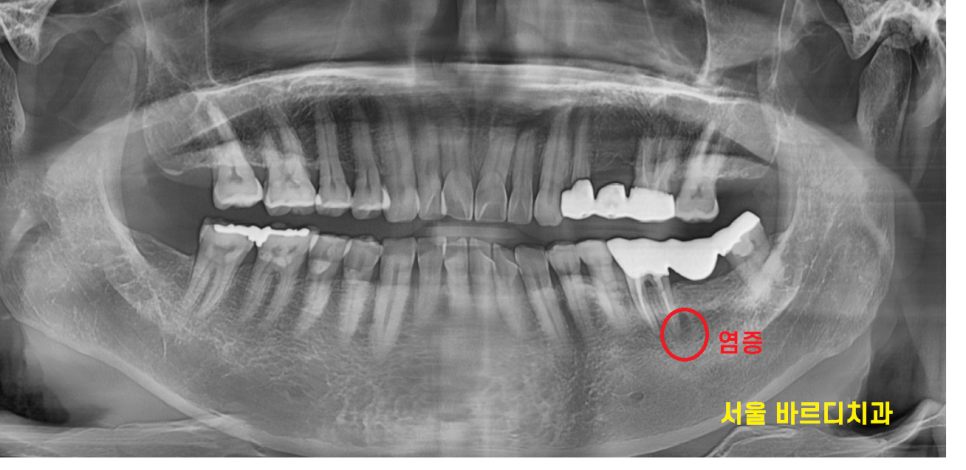

예전에 금니로 씌운 부분이

탈이 생겼는데

환자분은 사랑니가 예쁘게 올라와서

사랑니와 묶어서 보철을 하신 상황이었습니다.

이렇게 예쁘게 올라와 잘 사용하시는 환자분이

몇 안계시는데 축복받으셨네요~

어쨋든간에 x-ray에서 농양이 보여서

자세히 보이는 사진을 한장 더 찍어보았습니다.